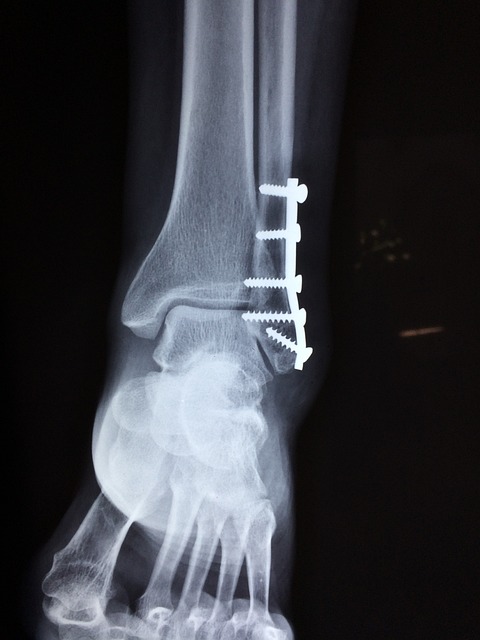

발목 부상에는 다양한 유형이 있는데, 각각 뚜렷한 원인과 증상이 있습니다. 일반적인 부상 중 하나는 발목을 접질린 것인데, 갑작스러운 비틀림 동작으로 인해 인대가 늘어나거나 찢어질 때 발생합니다. 발목 골절은 발목 관절에 하나 이상의 뼈가 부러지는 것을 수반하며, 종종 외상이나 높은 충격 사고로 인해 발생합니다. 아킬레스건 부상은 종아리 근육과 발뒤꿈치 뼈를 연결하는 힘줄이 긴장되거나 파열될 때 발생하며, 일반적으로 빠른 가속이 필요한 활동에 종사하는 선수들에게 영향을 미칩니다.